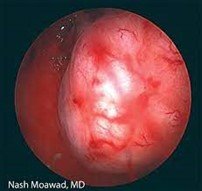

-هیستروسکوپی: این یک معاینه و جراحی غیر تهاجمی از کانال دهانه رحم و داخل رحم با استفاده از ابزار بینایی (هیستروسکوپ) است که از طریق واژن وارد می شود و معمولا نیاز به بیهوشی و انجام در اتاق عمل دارد.

-میومکتومی هیستروسکوپی: در طی این روش سرپایی، پزشک از دوربینی استفاده میکند که از طریق واژن وارد میشود تا بخشهای قابل مشاهده تومورهای فیبروئید را بتراشد. این روش فقط فیبروم هایی را که در داخل حفره رحم ایجاد شده اند درمان می کند.